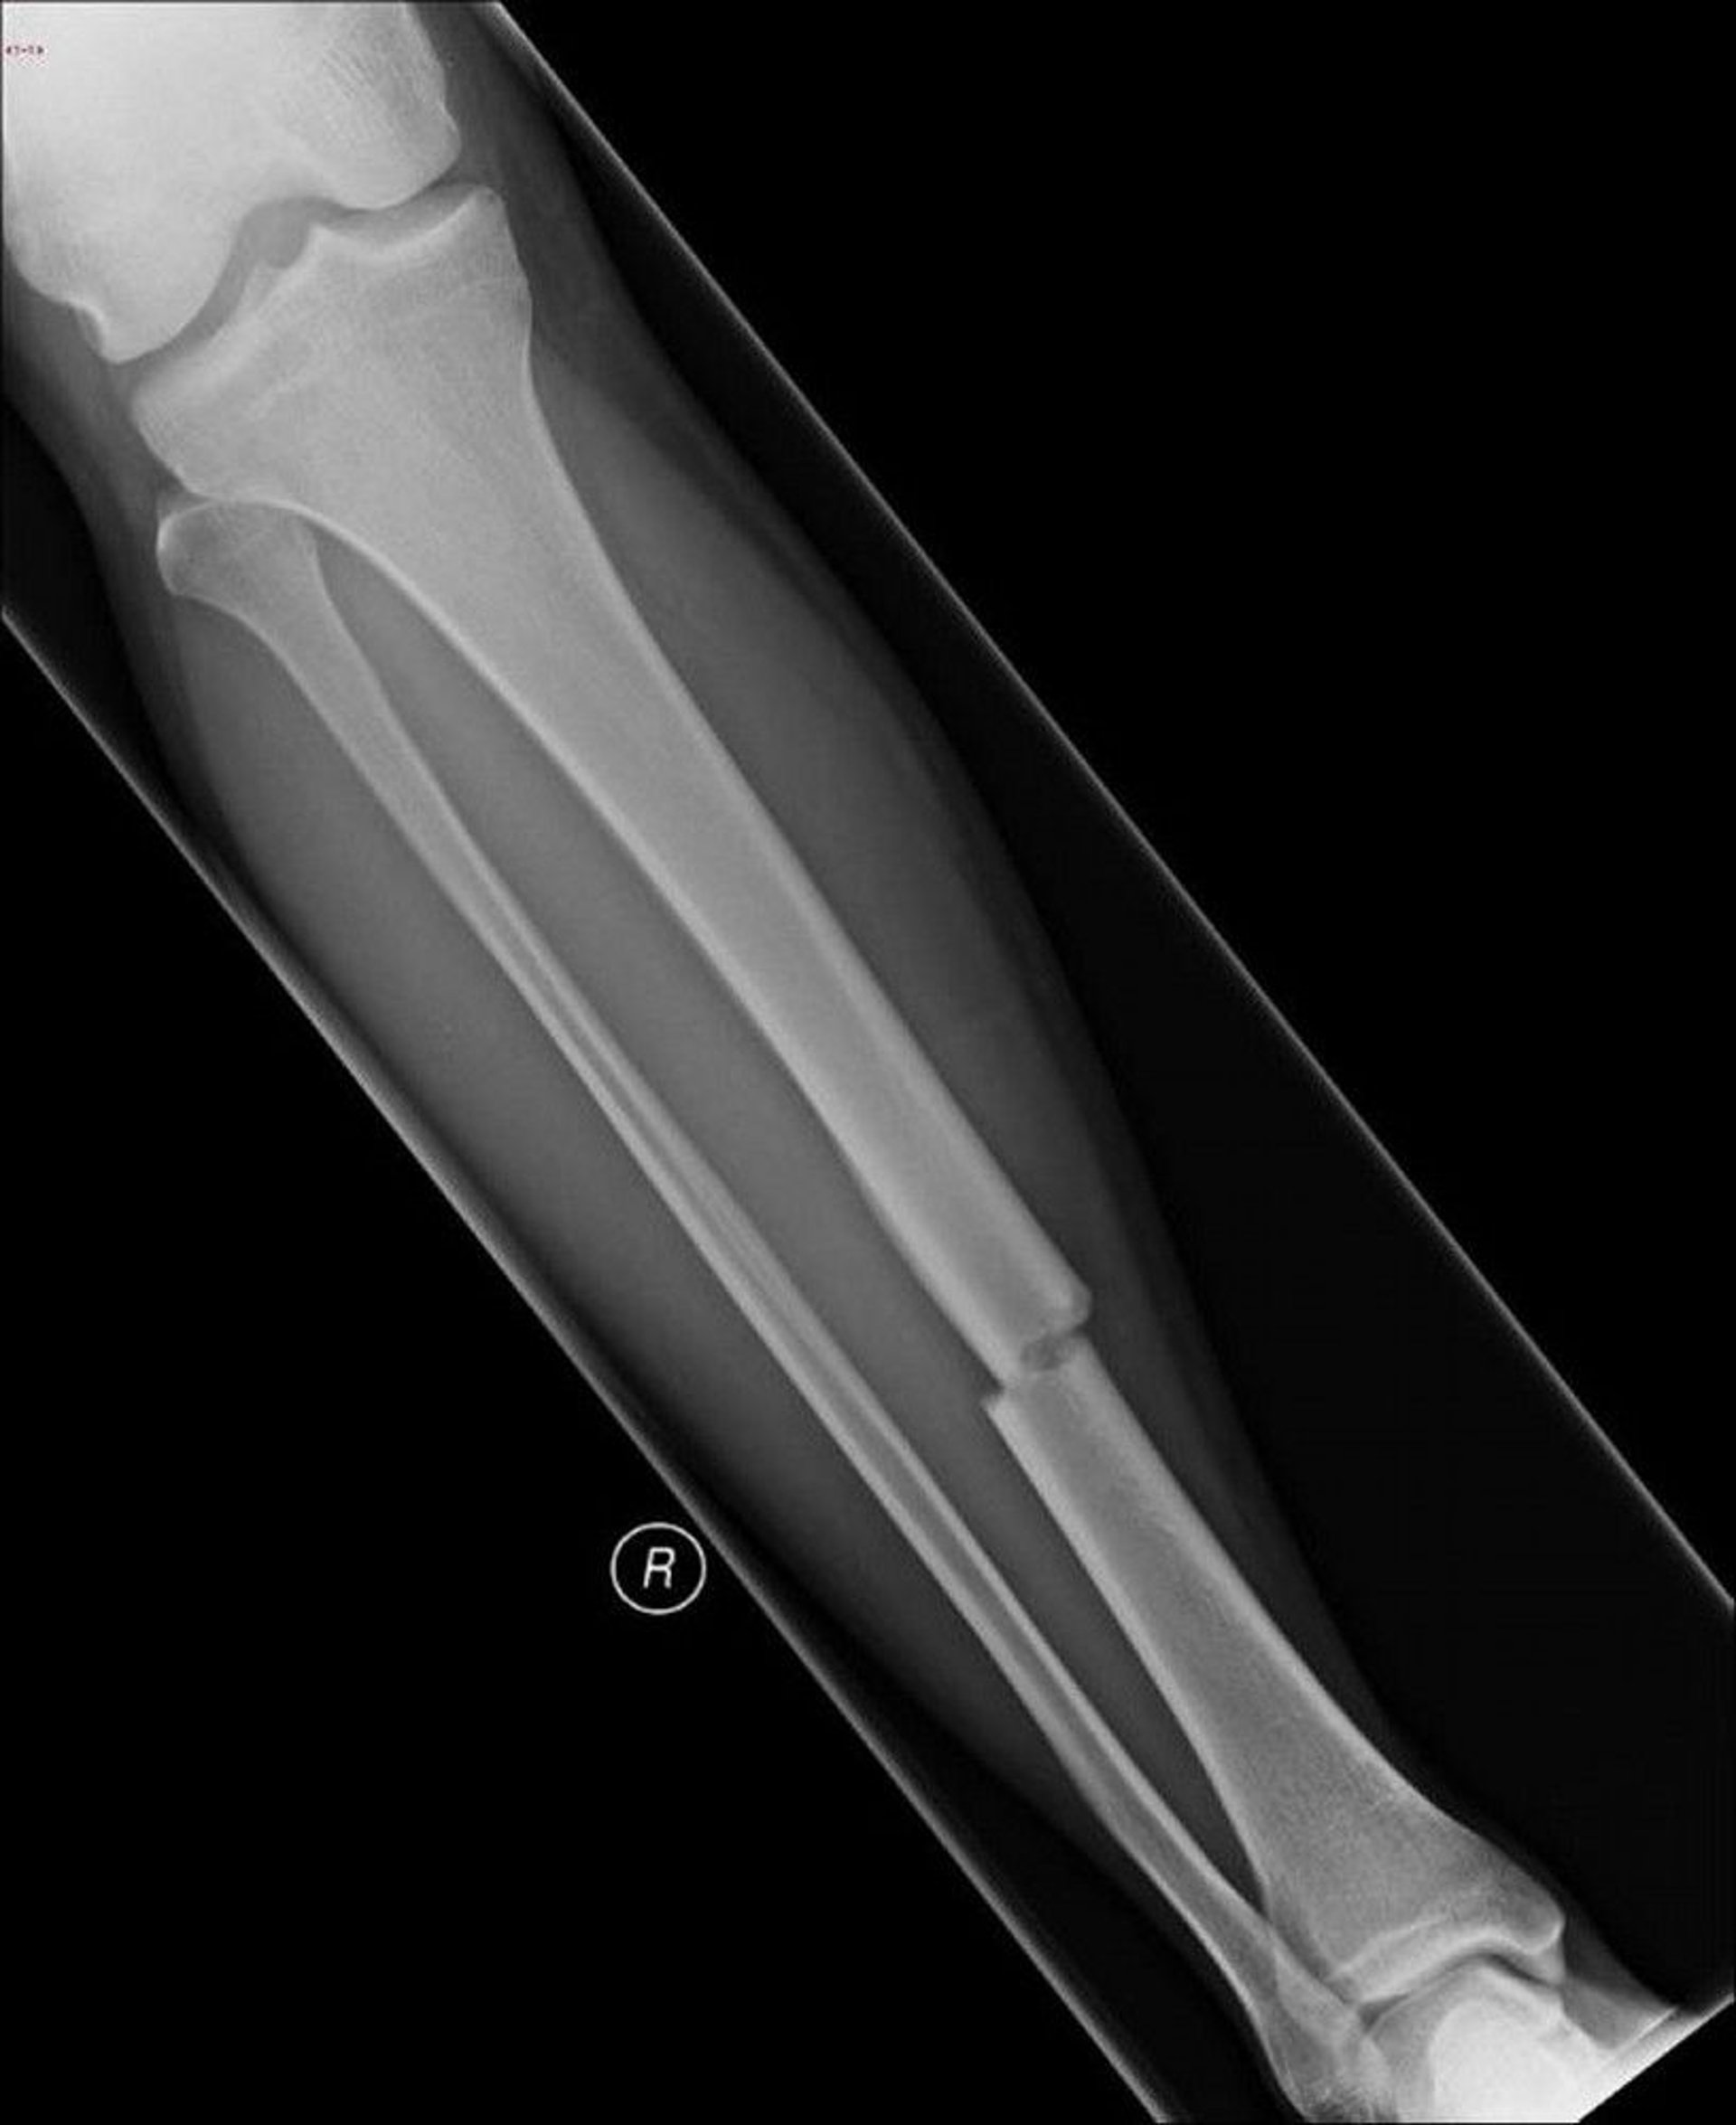

This x-ray shows a break in the middle of the shin bone (tibia).

Image courtesy of Danielle Campagne, MD.